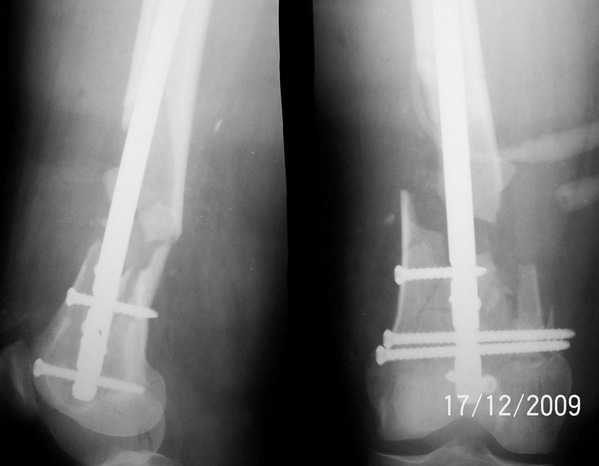

Уважаемые коллеги, прооперирована пациентка антеградным штифтом Остеомед, костная

пластика не проводилась. Выбранный штифт по каналу бедренной кости на фоне отсутствия

переднего кортикала в канале не центрируется. Технически неприятно, отсутствие передней и

внутреннебоковой стенки до зоны мыщелков сильно затрудняло репозицию. Получилась вот

такая картина. После стабилизации - очевидное повреждение ПКС и боковая нестабильность. В

общем и далее будет чем заняться. Нам и в дальнейшем будет очень интересно мнение коллег.